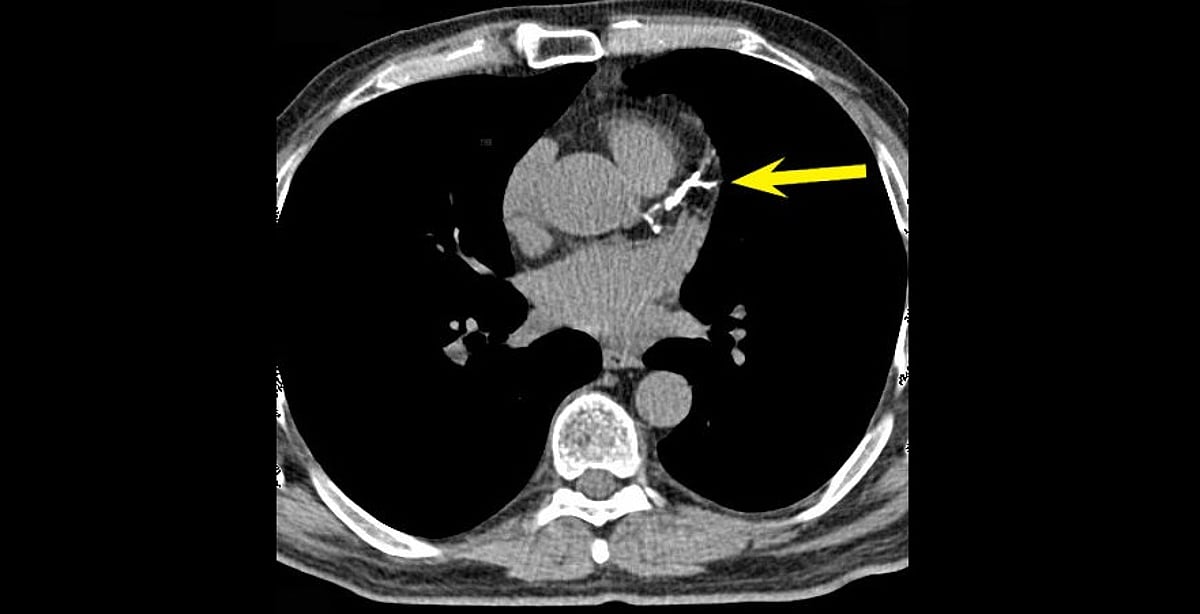

"النمر": تكلّس الشرايين قد يرتفع 25٪ سنويًّا دون خطورة.. واستخدام الأسبرين مشروط بـ3 عوامل

"النمر": تكلّس الشرايين قد يرتفع 25٪ سنويًّا دون خطورة.. واستخدام الأسبرين مشروط بـ3 عوامل

"النمر": تكلّس الشرايين قد يرتفع 25٪ سنويًّا دون خطورة.. واستخدام الأسبرين مشروط بـ3 عوامل